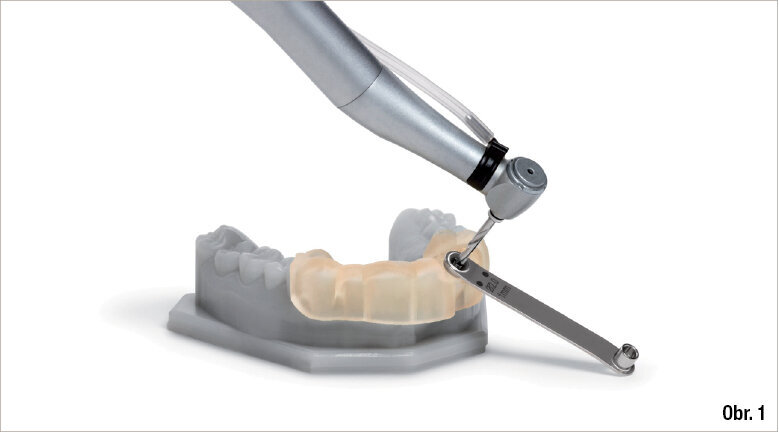

Obr. 1: CAD/CAM chirurgické šablony zcela omezují sklon vrtáku a hloubku preparace a jsou navrženy na základě dat týkajících se konkrétního pacienta z CBCT skenu a z intraorální kamery zpracovaných softwarem pro plánování implantátů